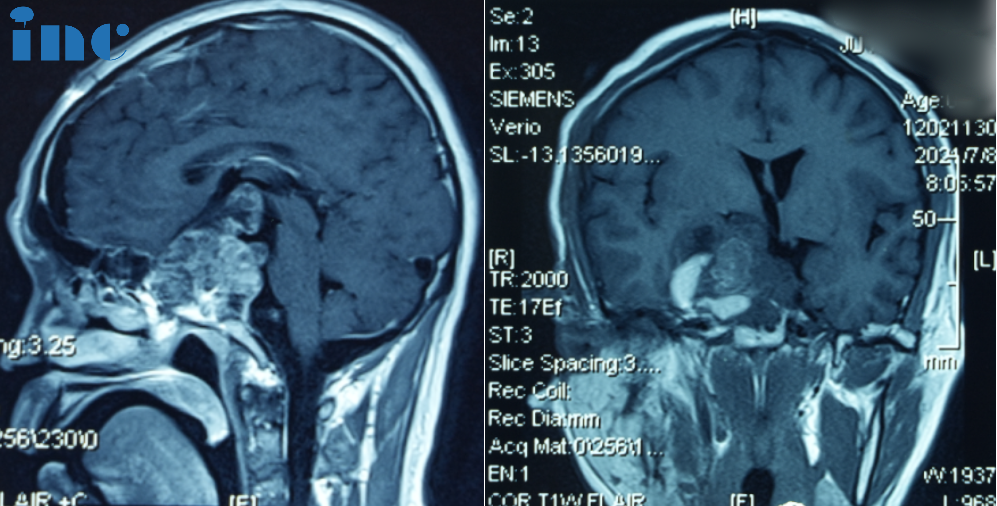

2019年10月患者无明显诱因下突发视野缺损,伴视力下降,遂就诊当地医院。行头颅增强MRI检查,提示鞍区占位性病变,脊索瘤可能性大。

同年12月,行全麻下经鼻神经内镜下肿瘤切除术,手术顺利。术后病理提示“脊索瘤”。术后恢复尚可,视力、视野恢复良好。后因新冠疫情原因,未做术后复查。

2021年,患者再次出现视力下降伴视野缺损。于当地医院行头颅MRI检查,提示“鞍区脊索瘤复发”。

2021年7月7日,全麻下行开颅鞍区肿瘤切除术,术后病理为“脊索瘤(复发)”。经过较长时间的术后恢复,患者视力、视野恢复正常。

2022年7月,患者三次出现视力下降/视野缺损症状,磁共振检查再次提示“鞍区肿瘤复发”。

因患者不想再接受开颅手术,10月8日全麻下行经鼻神经内镜下肿瘤切除术。术后病理为“脊索瘤(复发)”。术后出现嗜睡、精神萎靡等内分泌功能紊乱症状,同时伴脑积水。遂于11月19日行脑脊液V-P分流术,后症状缓解消失。

“5月8号咨询法国教授,然后到5月15号就手术了,真的很快、很及时。”苏先生一家选择手术时并没有太多犹豫,他们知道这一次机会来之不易。2023年5月15日,INC法国Froelich教授为苏先生做了四次开颅手术,在术中,Froelich教授联合应用显微镜和内镜,运用的“筷子手法”,术后当晚核磁显示肿瘤已基本全切。这对夫妻是幸运的,在这场风险较大、具挑战的手术中重获新生。

术后:手术顺利,术中将鞍上鞍内、海绵窦区、三脑室肿瘤切除